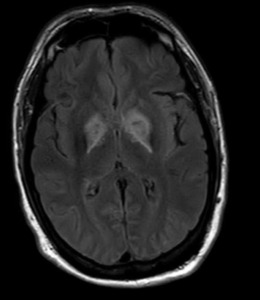

Further reevaluation of the patient’s initial head CT noted bilateral hypodensities in the globi pallidi (Figure 1). An MRI was ordered, revealing restricted diffusion on diffusion weighted imaging with symmetric bilateral involvement of the globi pallidi (GP). Hypointensity to surrounding brain parenchyma was noted on T1 Axial MRI, with corresponding hyperintensity on T2 Axial MRI. MRI films are included in this report (Figures 2 and 3). An arterial blood sample revealed a carboxyhemoglobin (COHb) level of 3.8% (above the absolute upper normal limit of 3% for smokers). Per his wife, the patient had smoked one to two packs of cigarettes daily for the past 18 years.

The GP, a deep subcortical structure at the inferior base of the brain, is the most frequently affected structure in CO poisoning and usually damaged immediately, symmetrically, and bilaterally.16 The leading theory for why CO specifically targets the GP is that it contains the highest iron content in the brain.17 The ischemic CO induced lesions in the bilateral GP of the basal ganglia can be seen as symmetric hypodensity on CT, hyperintensity on T2, hypointensity on T1, and restricted diffusion on diffusion weighted imaging MRI. The patient described in this case report demonstrated these classic findings on imaging that ultimately confirmed the diagnosis (Figures 1, 2, and 3).